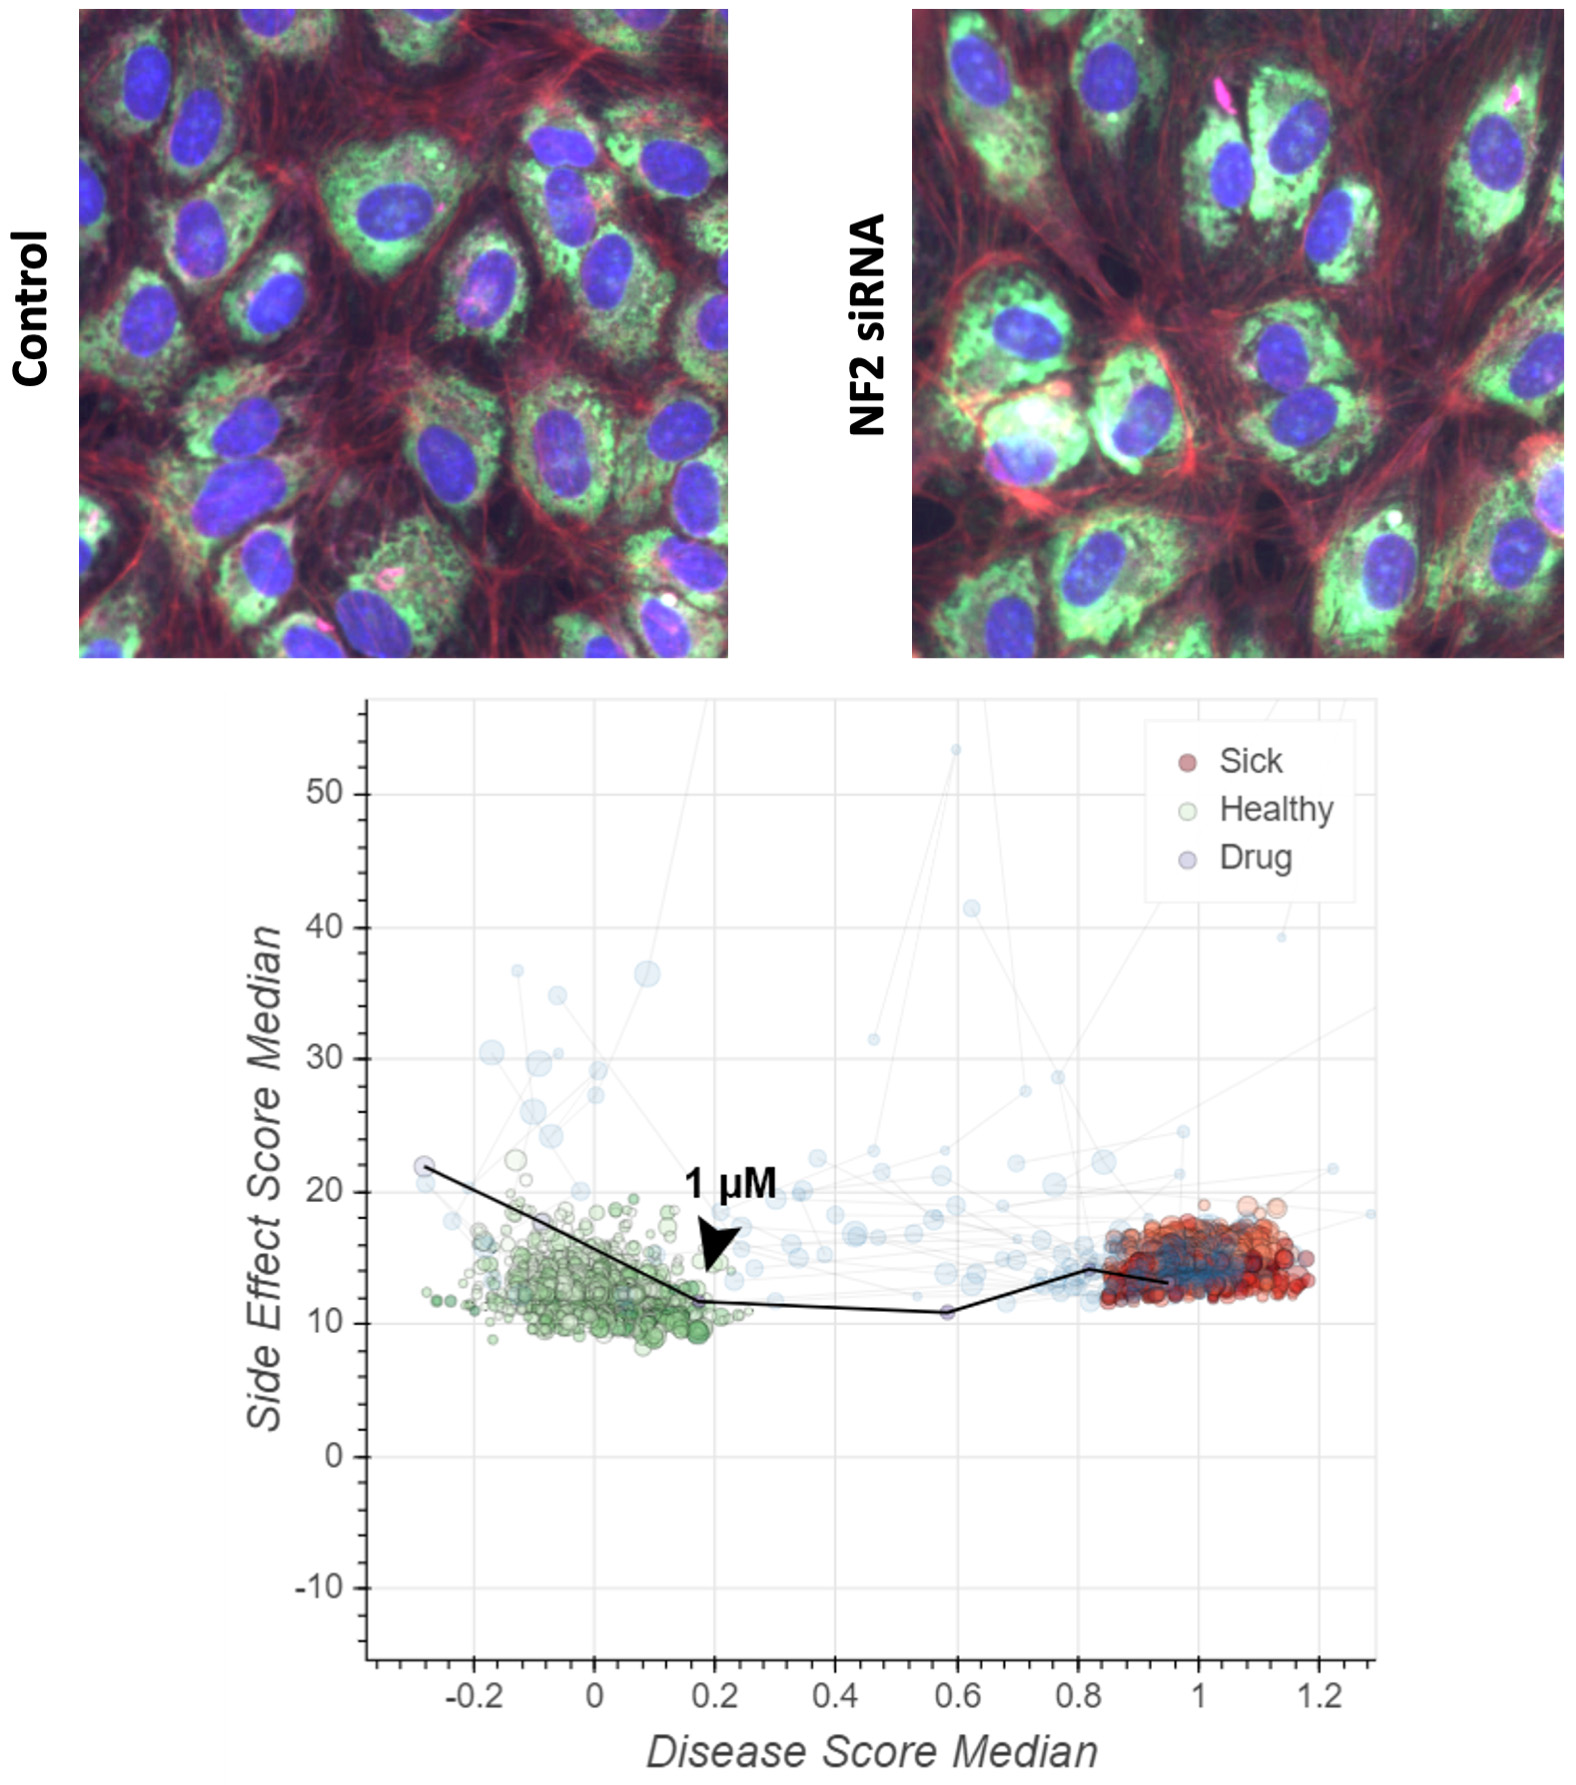

At Recursion, we are pioneering the integration of innovations across biology, chemistry, automation, data science and engineering to industrialize drug discovery in a full-stack solution across dozens of key workflows and processes critical in discovering and developing a drug. For example, by combining advances in high content microscopy with arrayed CRISPR genome editing techniques, we can rigorously profile massive, high-dimensional biological and chemical perturbation libraries in multiple human cellular contexts to create digital ‘maps’ of human biology. Leveraging advances in scaled computation, we can conduct massive virtual screens to predict the protein targets for billions of chemical compounds. Similarly, data generated from our automated DMPK module and InVivomics platform enables us to predict ADME properties and identify toxicity signals, respectively, significantly faster than traditional methods. We believe that by harnessing advances in technology to industrialize drug discovery, we can derive novel biological insights not previously described by scientific researchers, reduce the effects of human bias inherent in discovery biology and reduce translational risk at the program outset.